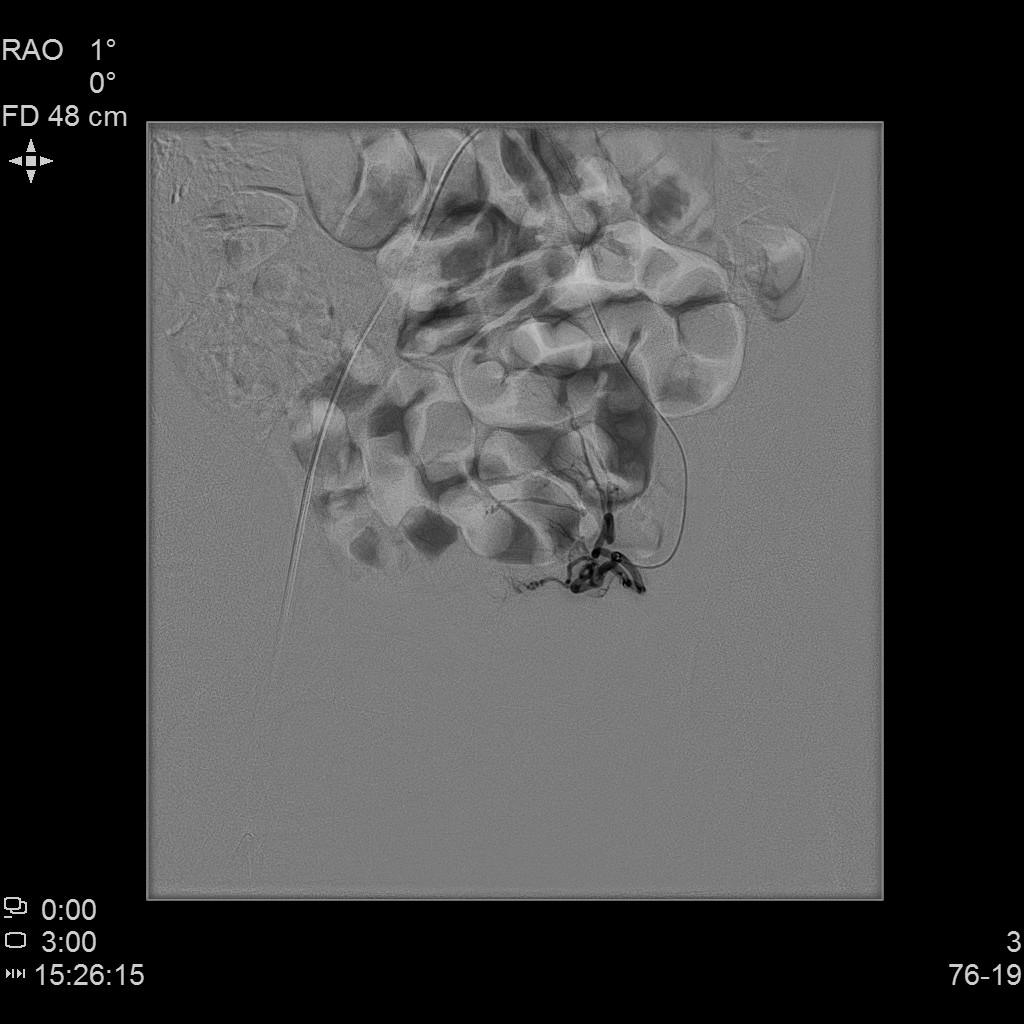

例3

中年患者,发现“子宫腺肌症”10年余,近5年痛经、月经量增多等症状明显加重,导致贫血,严重影响生活质量。

• 术前彩超、磁共振检查显示子宫明显增大,子宫前壁可见弥漫型子宫腺肌症病灶,合并粘膜下、肌壁间子宫肌瘤。

• 经左桡动脉穿刺置管,DSA下行双侧子宫动脉栓塞治疗。

左侧子宫造影

右侧子宫动脉造影